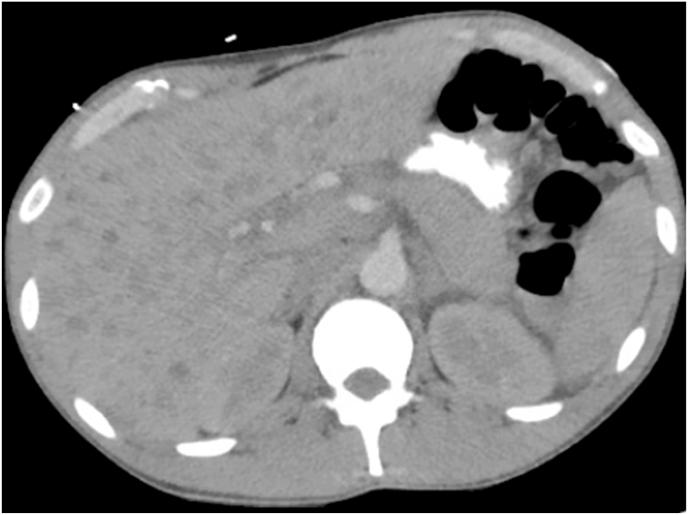

Barriers posed by the COVID-19 pandemic have led to reduced access to Human Immunodeficiency virus (HIV) care, leaving untreated patients at risk for various superimposed infections and malignancies such as Kaposi sarcoma (KS). We recently encountered a 37-year-old African-American male with a past medical history of HIV who tested positive for SARS-CoV-2 and was diagnosed with AIDS-related disseminated KS, representing the first reported case of COVID-19 infection with a newly diagnosed concomitant KS. The patient experienced multi-organ failure requiring tracheostomy, renal replacement therapy, and a prolonged intensive care unit (ICU) stay. Goals of care were changed to comfort measures and the patient passed away shortly afterwards. He was made comfort measures and passed away shortly afterwards. AIDS-related KS is a vascular tumor seen in association with (HHV-8). Management of limited AIDS-related KS typically includes combined antiretroviral therapy (ART) while multi-organ KS disease demands systemic chemotherapy. Immunosuppression should be avoided in patients with AIDS-related KS as it can lead to progression of KS. This recommendation is in conflict with the usual standard of care for patients with COVID-19 pneumonia, requiring clinical judgment and a customized approach based on the stage and severity of both the KS and the COVID-related disease. We briefly review HIV-COVID-19 coinfection, AIDS related KS and challenges associated with their management.

2019年冠状病毒病(COVID-19)大流行造成的障碍导致获得人类免疫缺陷病毒(HIV)治疗的机会减少,使未经治疗的患者面临各种叠加感染和恶性肿瘤的风险,如卡波西肉瘤(KS)。我们最近遇到一名37岁的非裔美国男性,他有HIV病史,SARS-CoV-2检测呈阳性,被诊断为艾滋病相关播散性KS,这是首例报告的COVID-19感染合并新诊断KS的病例。该患者出现多器官功能衰竭,需要气管切开、肾脏替代治疗,并在重症监护病房(ICU)长期住院。护理目标改为采取舒适措施,患者随后不久去世。对他采取了舒适措施,他随后不久去世。艾滋病相关KS是一种与人类疱疹病毒8型(HHV-8)相关的血管肿瘤。局限性艾滋病相关KS的治疗通常包括联合抗逆转录病毒疗法(ART),而多器官KS疾病则需要全身化疗。艾滋病相关KS患者应避免免疫抑制,因为这可能导致KS进展。这一建议与COVID-19肺炎患者的通常护理标准相冲突,需要根据KS和COVID相关疾病的阶段和严重程度进行临床判断并采取定制方法。我们简要回顾了HIV与COVID-19合并感染、艾滋病相关KS及其管理相关的挑战。